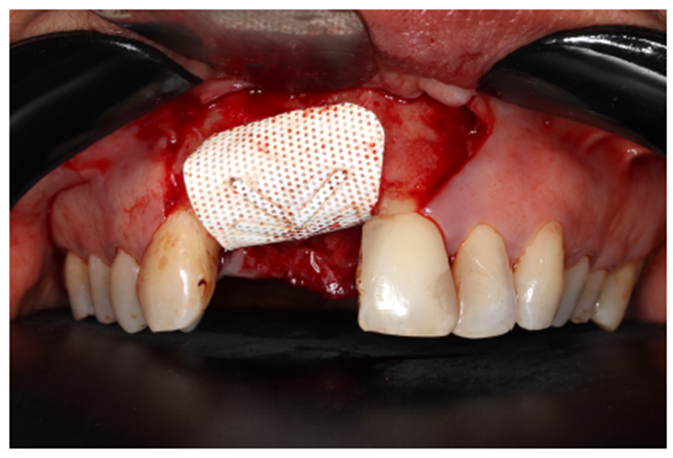

Nos casos de extensa reconstrução óssea, o retalho cirúrgico deve ser realizado à distância para visualização total da área cirúrgica, acomodação do seu futuro material de enxerto, ganho e fechamento total do tecido mole (Figura 4). Outro ponto importante para o sucesso da integração do material de enxerto é a descorticalização do processo alveolar, a fim de levarmos sangue medular com maior quantidade de células osteoprogenitoras. No caso, foi realizado com uma broca tipo lança.

Após a descorticalização, a membrana de PTFE-d (Cytoplast) foi aberta para modelagem e adaptação no rebordo, visando o acomodamento do material de enxertia. Ela foi parafusada na cortical palatina facilitando a inserção do material via vestibular. (Figuras 5 e 6).